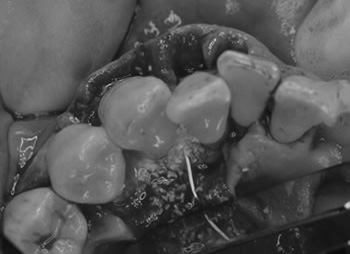

After

歯の周りには、歯周組織、骨が再生され歯周ポケットは3mmになりました。